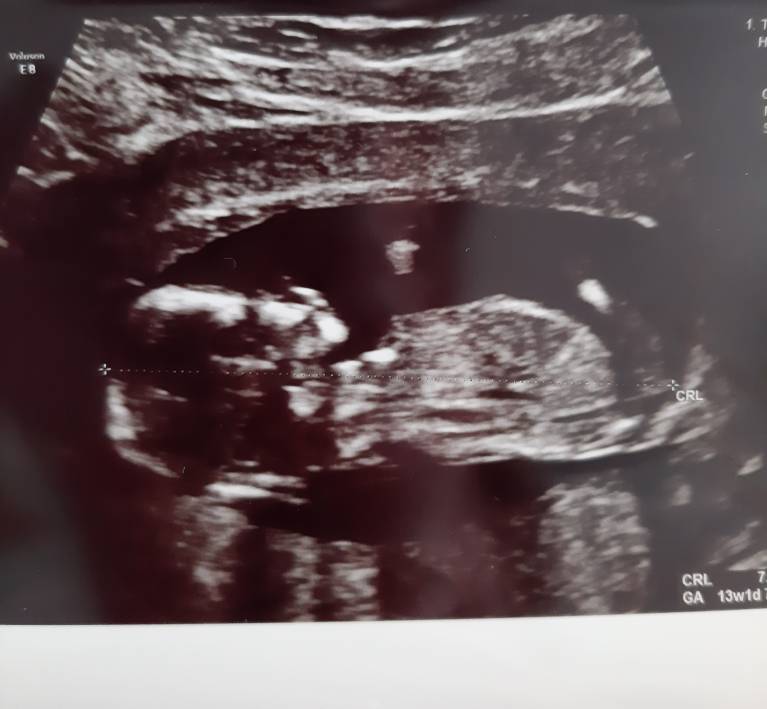

A właśnie, u mnie coś widać ? Bo ja się nie znam [emoji6] może coś juto będzie widać , chociaż sprzet gorszy będzie[emoji86]Zobacz załącznik 1130584

Nie widać niestety,może jutro uceluje na zdjęciu. Trzymam kciuki za wizytę✊